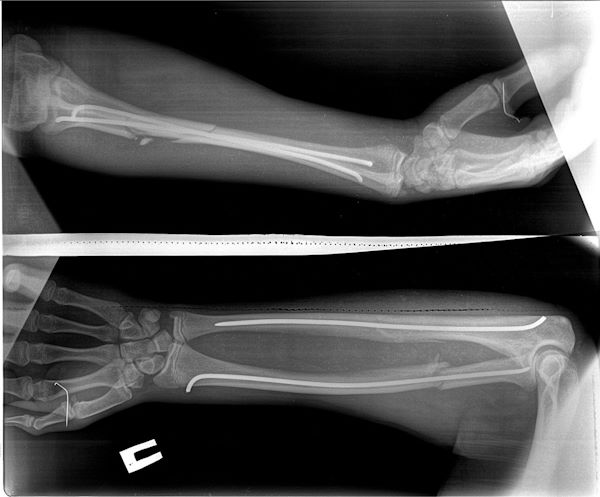

Накануне в одном из пригородных районов 14-летний подросток на мотоцикле столкнулся с автомобилем. Ребёнка госпитализировали в отделение анестезиологии и реанимации, после перевели в отделение травматологии и ортопедии. У пострадавшего различные виды переломов рук и ног, черепно-мозговая травма, рвано-ушибленные раны и т.д.